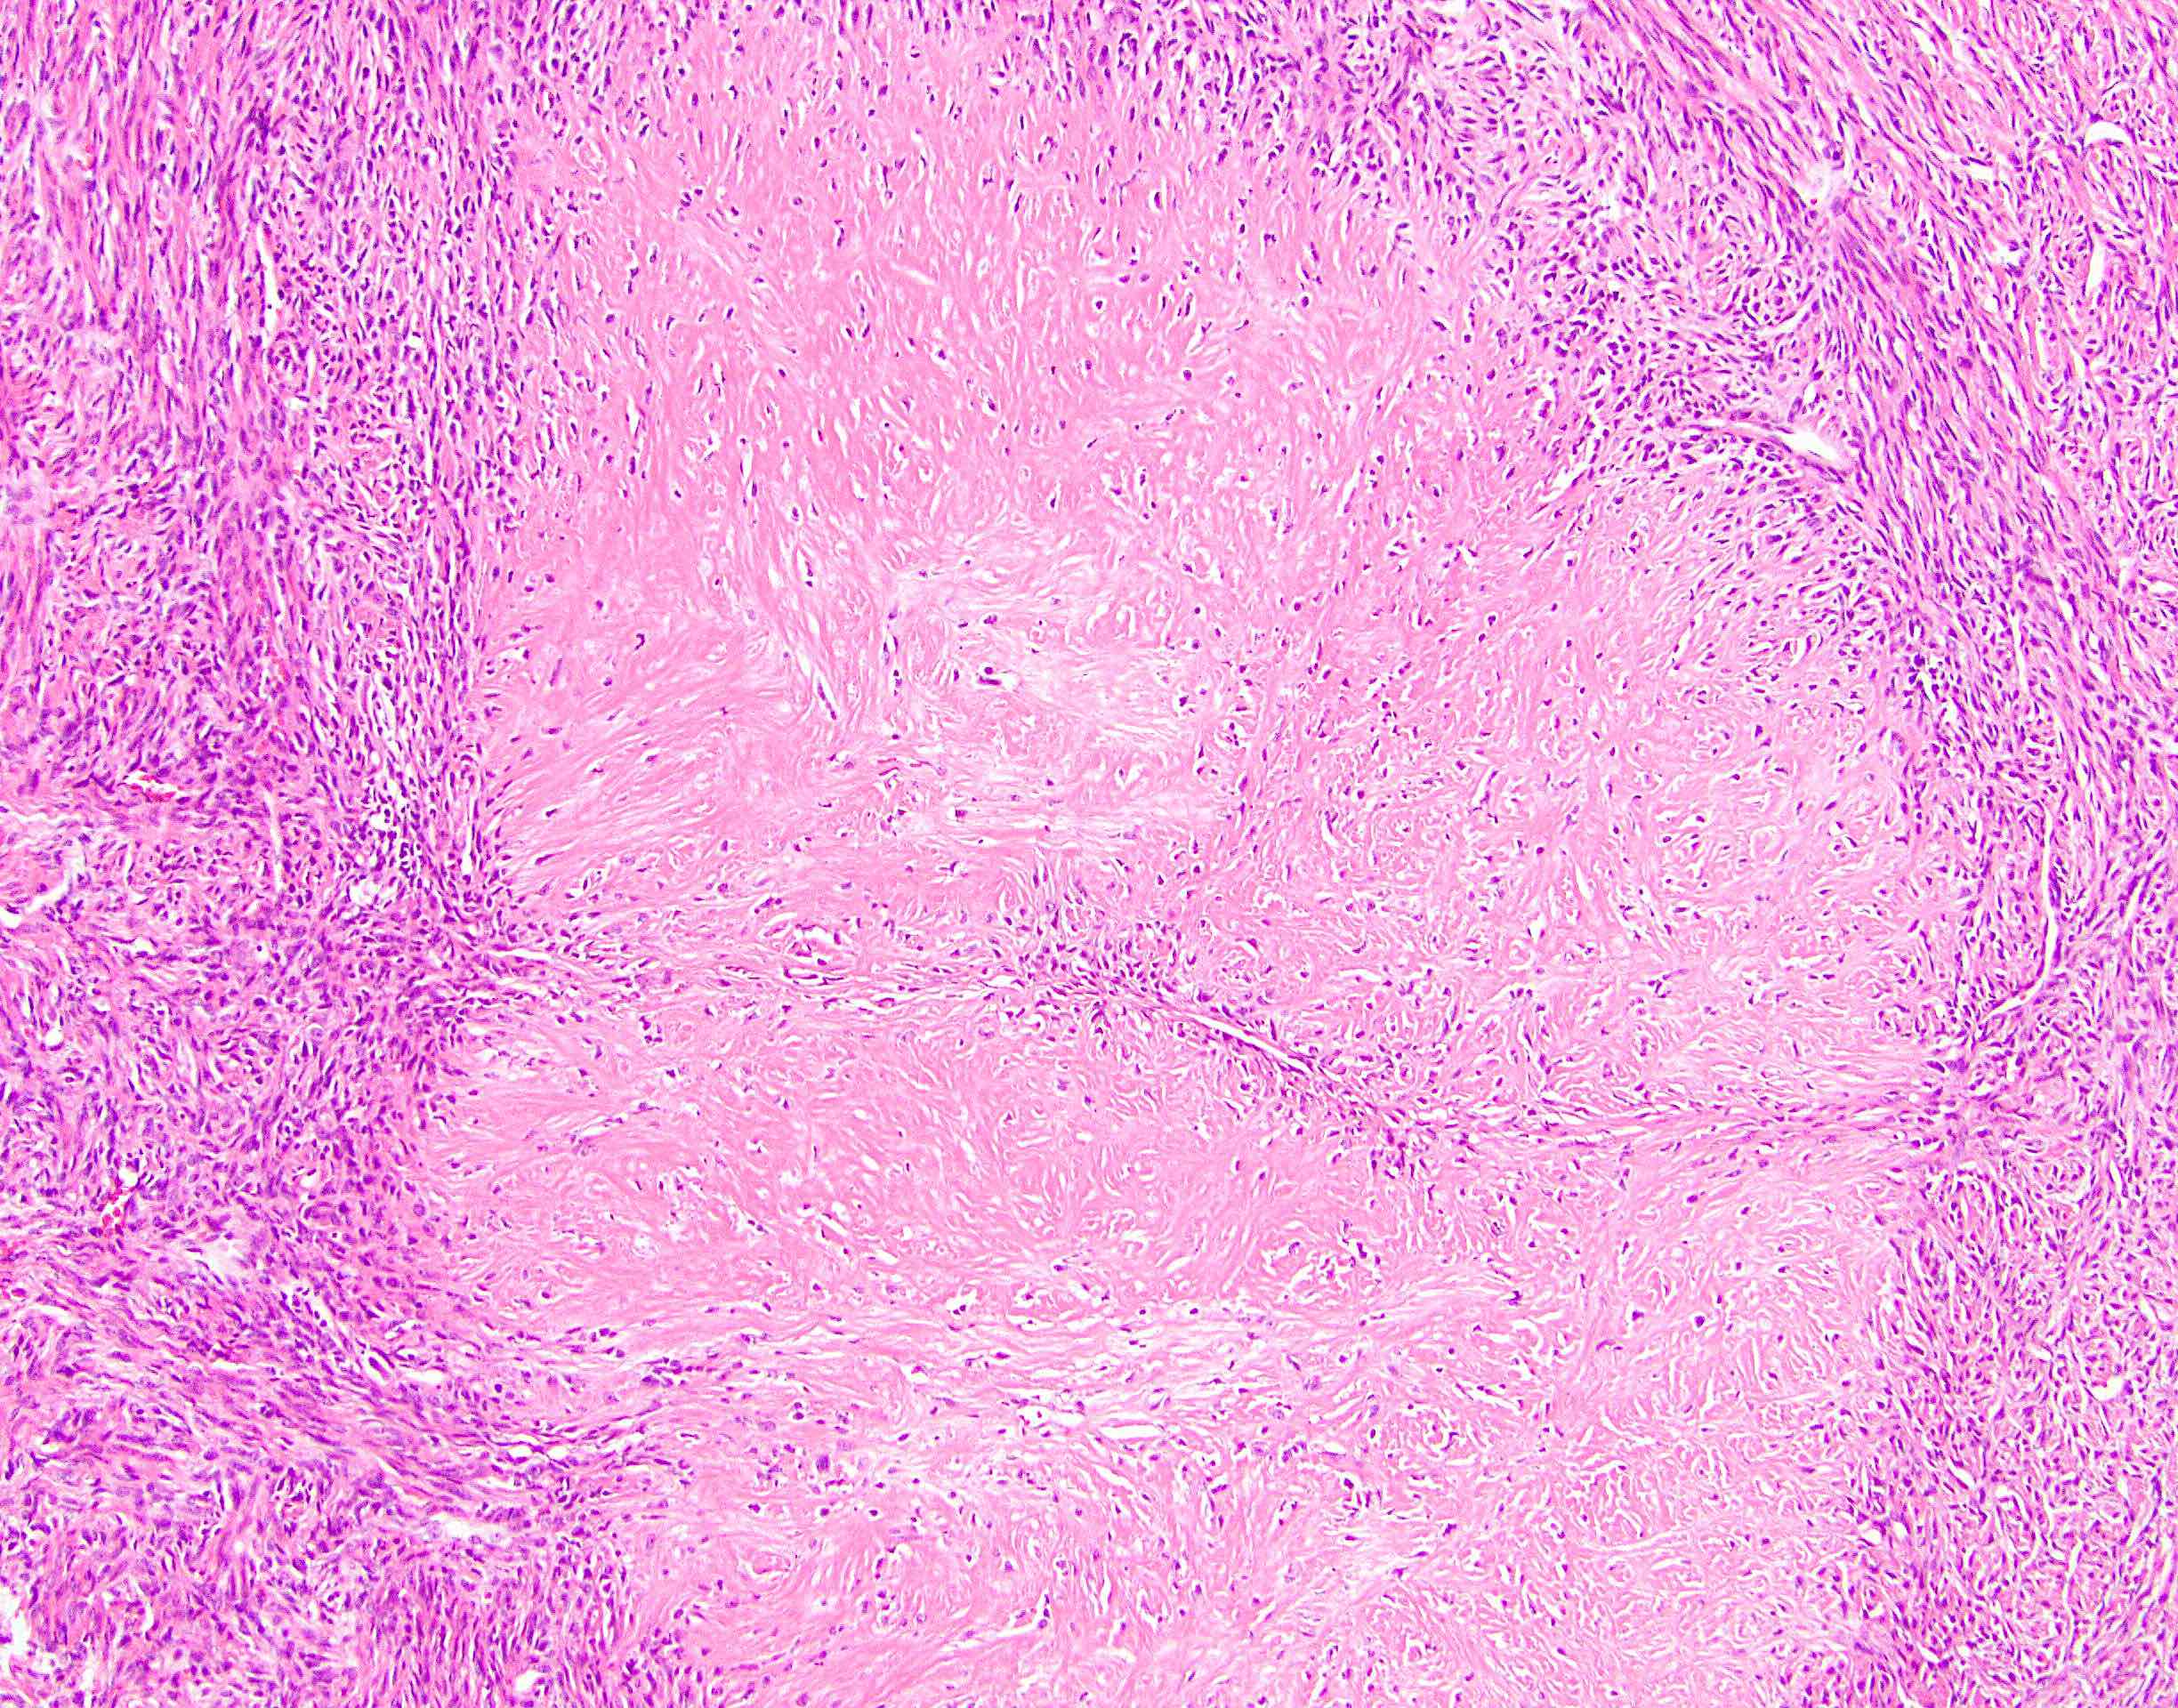

Microscopic (histologic) description

- Low to moderately cellular, bland fusiform or spindled cells with focal to diffuse whirling in heavily collagenized stroma with abrupt transition to myxoid areas

- 45% have epithelioid areas

- 40% contain poorly formed but large collagen rosettes

- Often infiltrates adjacent skeletal muscle

- Occasionally has areas of increased cellularity, atypia, necrosis or mitotic activity characteristic of intermediate to high grade sarcoma

- Recurrences may show increased cellularity and mitotic activity

Microscopic (histologic) images